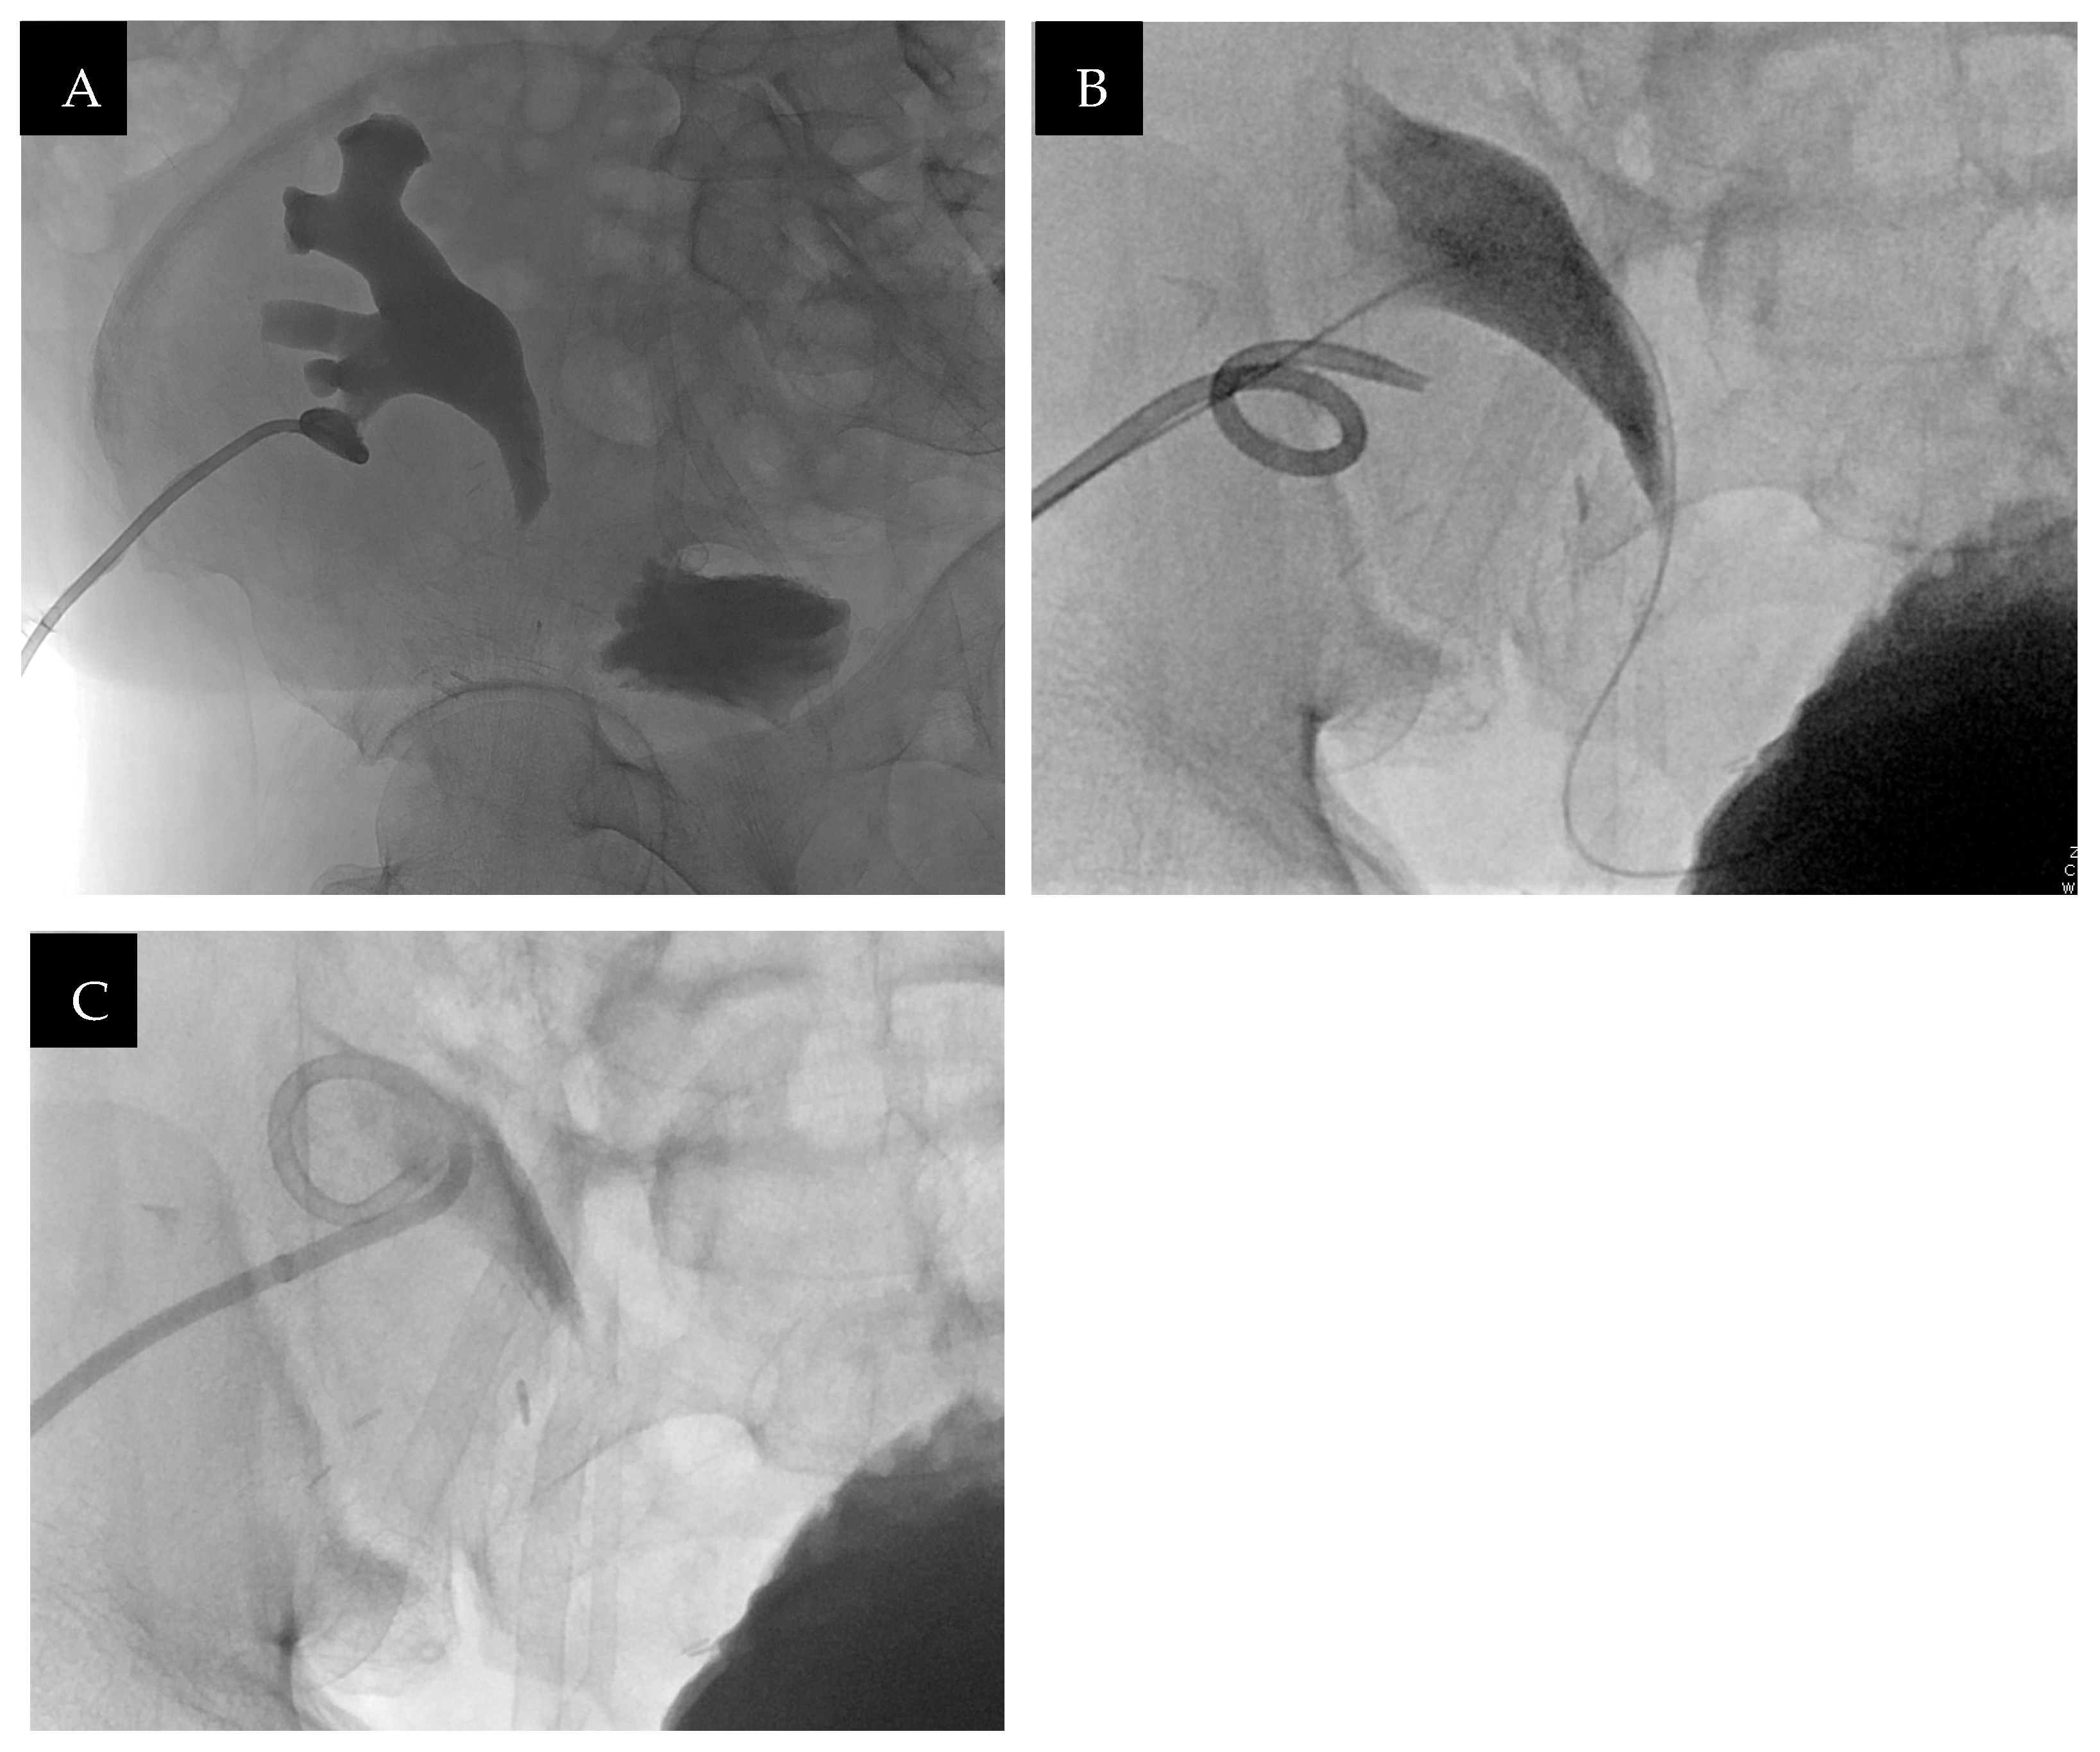

After completing additional courses of antibiotics for two subsequent urinary tract infections, the decision was made to proceed with the PCNL. The procedure started as planned with interventional radiology performing a nephrostogram, which demonstrated hydroureteronephrosis, heterogeneous filling defects within the proximal collecting system, and no obvious renal stones (Figure 7). A hydrophilic guidewire advancement through the nephrostomy tube and resulted in improved contrast drainage into the bladder. The nephrostomy tube was then exchanged and near-complete contrast drainage was seen. Due to the likely passage of the dense, calcified material within the collecting system and improved drainage, the decision was made to postpone the PCNL and monitor the patient with the nephrostomy tube clamped. CT imaging on the same day demonstrated a small amount of calcification and hyperdense debris within and distal to the nephrostomy tube coil (Figure 8). On post-procedure day 1, he developed sepsis, requiring antibiotics. The nephrostomy tube was opened to gravity. After resolution of sepsis, the nephrostomy tube was re-clamped. The patient tolerated the clamp trial and was discharged with culture-sensitive antibiotics. Renal function remained stable 3 weeks after the nephrostomy tube was clamped, so it was removed. Four months after nephrostomy tube removal, the patient remained asymptomatic, with creatinine of 1.1 mg/dL and eGFR 70 mL/min/1.73 m2 and no further urinary tract infections.

Figure 7. (A) Antegrade nephrostogram from previously placed percutaneous nephrostomy tube demonstrated moderate hydroureteronephrosis with a transition point in the proximal ureter and limited contrast to the bladder. (B) Antegrade guidewire advancement, which resulted in improved contrast drainage. (C) Replacement of the percutaneous nephrostomy tube with near-complete contrast drainage into the bladder and small residual heterogeneous filling defect.